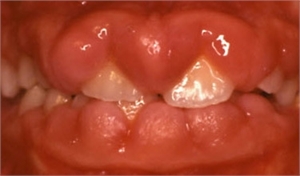

Enlargement of gums or gingiva is called gingival hyperplasia in the dental terms. This condition occurs due to abnormal multiplication of gingival tissue cells caused by various factors. Typical findings for gingival hyperplasia are swollen and enlarged gums. If you are suffering from gingivitis there will be gum bleeding as well as tenderness. The teeth get covered with the gums if the infection is too intense.  The patient is examined by a dentist and then the patient is sent for further examination if any further complications are seen.

There are several causes of gingival hyperplasia. Inflammatory and granulomatous disorders like Hand-Schuller-Christian syndrome, auto-immune disorders like plasma cell gingivitis which is associated with allergic and collagenous nature, neoplastic disorders like acute leukemia and monocytic leukemia are some of the causes of gingival hyperplasia. Other causes include metabolic and storage disorders like aspartylglycosaminuria, genetic disorders like Cross syndrome. One of the most important causes of gingival hyperplasia is toxicity of drugs. Drug induced gingival hyperplasia is a condition which occurs due to excess of deposition of drugs given to a patient. It is also called as Drug Induced Gingival Overgrowth (DIGO). Immunosuppressant like Cyclosporin, anticonvulsants like valproate, phenytoin, phenobarbital, primidone and calcium channel blockers like nifedipine, verapamil and amlodipine are the drugs which cause gingival hyperplasia when the doses exceed. Cyclosporin and phenytoin toxicity are the important toxicities caused in a patient especially in case of dental plaque where these drugs get deposited on the tooth. Different individuals are susceptible to different drugs. In general, it has been observed that the keratinocytes and fibroblast are susceptible to phenytoin, cyclosporine and many a times to nifedipine and amlodipine.  The susceptibility rates of the patient to these drugs depend on the metabolism of the body, age, sex and their health history too.